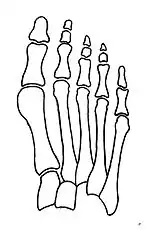

Primus varus deformity

Primus varus deformity is the leaning of the first metatarsal bone away from the second metatarsal and towards the opposite foot (Fig. 1). As it leans over, its head sticks out to form the bunion bump and it also widens the forefoot to cause shoes feeling too tight. Thus when bunion pain becomes unmanageable, surgical correction is to narrow the forefoot by repositioning of the first metatarsal head back to its normal position. This can be done by osteotomy (bone-breaking), soft tissue (non-osteotomy) or fusion techniques.